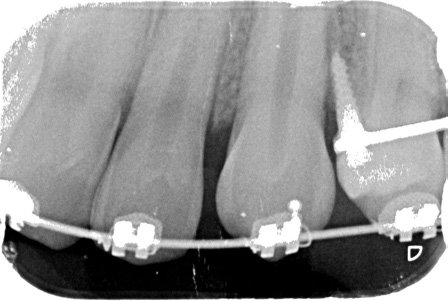

Preadjusted .022" × .028" brackets*** were placed in the upper arch, and an .014" nickel titanium archwire was used to correct the upper incisor inclination and the scissor bite (Fig. 2). After five months of treatment, a Herbst appliance with four 1.4mm × 6mm TADs† (H4T) was placed (Fig. 3). In the lower arch, one miniscrew was inserted between the right first permanent molar and second premolar and the other between the left first and second premolars. Auxiliary buttons were bonded to the buccal surfaces of the canines, and elastic chains were attached to the miniscrews to retrocline the lower incisors and promote mandibular protraction. In the upper arch, a miniscrew was inserted between the first and second premolars on each side, and elastic chains were attached between the miniscrews and an .018" × .022" stainless steel archwire for vertical control.

Fig. 2 .022" × .028" brackets*** placed in upper arch.